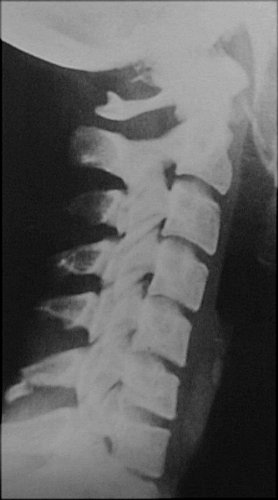

Return to Clay Shoveler's Fracture